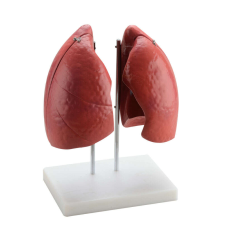

1 kép OEM Anatómiai Tüdőmodell - 4 Rész - Élethű - 57x46x62cm

Élethű 4 részes tüdőmodell: Tanulmányozd a légzőrendszer anatómiáját! 🫁 Ez az élethű tüdőmodell kiváló eszköz az emberi légzőrendszer részletes tanulmányozásához. Négy részből áll, így könnyedén megvizsgálhatóak a tüdőlebenyek, a vénák és az artériá...